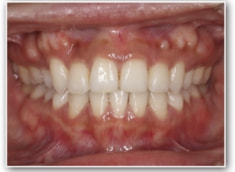

治療後